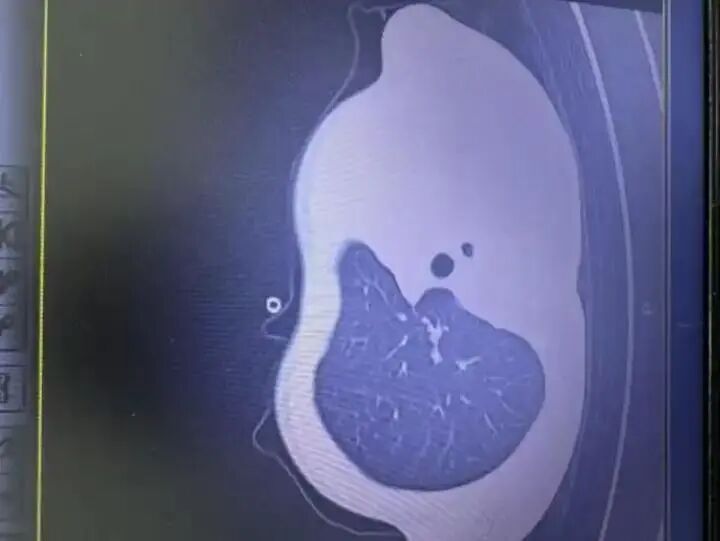

浙江11岁男孩因流感进了ICU 肺里堵满"痰栓" 12月1日早上,11岁男孩小宇(化名)发烧到38.9℃,伴有轻微咳嗽和喘息。家人以为只是感冒,就给 孩子吃了药,却没想到病情会在一天内急转直下。到1号晚上,小宇咳嗽加剧,喘得越来越急,还喊胸 口疼,没法躺平。 2日早上,小宇出现呼吸急促、嘴唇发紫、精神不振,家人急忙将他送到浙江大学医学院附属儿童医院 急诊,胸片检查发现左肺已变"白肺",随时有窒息危险。由于病情凶险,小宇被紧急送进PICU(儿科重 症监护病房)。在气管镜下,医生发现小宇的气道里堵满了树枝状的"痰栓",呼吸通道完全被塞住,气 道内壁还有坏死组织。在ICU的10天里,小宇先后做了5次气管镜,重复冲洗、清理新形成的"痰栓"和 坏死组织,同时进行抗感染、抗炎等治疗。直到12月12日小宇才转入普通病房,目前恢复良好。 "白肺"到底是什么? "早上开始发烧 晚上肺就白了" 近日 我们习惯性地把发热、咳嗽、乏力归为"感冒"范畴,但肺部感染的早期表现往往与普通感冒极其相似, 这正是问题的关键所在。 某些病毒性肺炎在感染初期表现温和,但病程却异常迅猛。尤其在免疫反应过度或病毒复制速度极快的 情况下,肺泡渗出液体和 ...